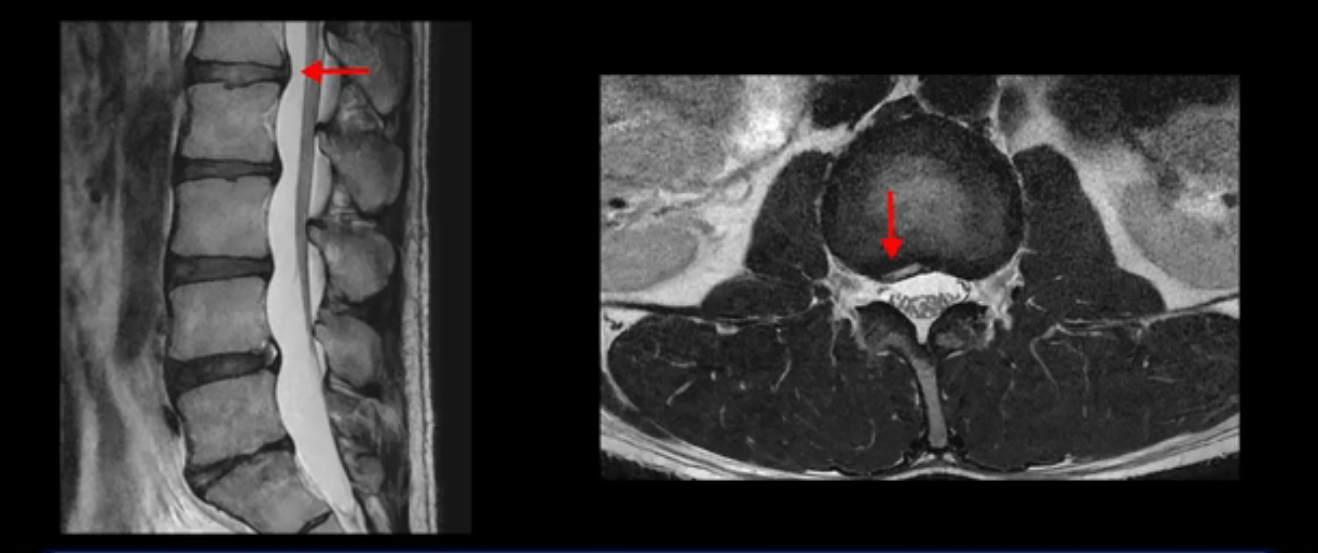

그런데 이분의 증상과 MRI가 전혀 일치하지 않는데, 왜 그런지 지금부터 자세히 설명드립니다. 이분 증상은 앉으면 엉치와 허리가 심하게 아파 10분 이상 앉는 게 어렵고 양쪽 발가락이 앉아있을 때나 누워있을 때 다 저립니다. 걸을 때도 아파서 10분 걷기도 어렵습니다. MRI를 마디마디 살펴보면 1번 2번은 오른쪽으로 살짝 밀려나온 디스크가 있지만 전혀 심하지 않고, 뒤에 또 설명하겠지만 최근에 밀려나온 급성 디스크가 아니고 오래된 디스크로 판단됩니다.

2번 3번도 비교적 디스크 상태는 좋고 신경 구멍 넓이도 아주 넓습니다.

3번 4번도 마찬가지로 디스크상태 좋아 보이고 신경 눌림 전혀 없어 보입니다.

앞서 1번 2번, 4번 5번, 5번 1번의 디스크가 찢어지고 조금 밀려 나온 게 최근에 찢어진 게 아니고 오래된 걸로 보인다고 말씀 드렸죠. 왜 그럴까요? 만약 급성으로 찢어진 것이라면 아주 심한 디스크성 통증이 있겠죠. 기침이나 재채기를 하면 심하게 아프고 허리를 조금만 구부리거나 비틀면 아주 날카로운 통증들이 생길 겁니다. 그런데 이분은 이런 증상이 전혀 아닙니다. 또 디스크의 밀려나온 정도도 전혀 심하지 않기 때문에 이분이 가지고 계신 양쪽 다리 저림, 특히 이분은 누워있을 때도 양쪽 발이 발가락까지 쑤신다고 하는데 이정도 디스크 때문에 그런 증상은 생길 수가 없는 겁니다. 이처럼 이분의 가벼운 디스크 탈출은 이미 오래 전에 진행되었고 섬유륜 자체는 이미 아문 상태인데도 디스크내장증을 진단받은 환자들 중에는 본인이 섬유륜 파열 환자라고 끝까지 믿는 분들이 많습니다. 다시 말하지만 디스크내장증이라는 진단을 받은 환자들을 보면 거의 전부 다 섬유륜 파열 증상이 아닙니다. 증상이 완전히 다릅니다. 진단이 애초에 잘못되면 어떤 치료를 받아도 좋아질 수 없습니다.

그럼 MRI를 자세히 봤으니까 이제 이 환자의 증상은 실제 왜 생기고 어떤 문제 때문에 아픈지에 대해서 차분히 설명을 드리도록 하겠습니다. 이 환자분의 진짜 통증의 원인은 무엇일까요? 이건 디스크의 문제가 아닙니다. 이 환자분의 진짜 통증의 원인은 허리의 기능이 완전히 무너진 겁니다. 허리의 기능 중에 가장 중요한 부분을 차지하는 게 근육인데, 이분의 근육 기능에는 오래 전부터 문제가 많았습니다. 이분은 작년에 앉지 못하고 양쪽 다리가 저리는 심각한 증상이 발생했는데요. 그런데 이런 증상이 발생하기 훨씬 이전부터 운동을 조금만 무리하면 허리가 뻐근하고 아픈 증상들이 있었습니다. 10년도 더 되는 오랜 기간 동안 허리가 조금씩 아프고 만성적으로 안 좋은 상태였는데, 6개월 전 어느 날 무리한 운동을 한 후에 허리와 근육의 기능적인 문제가 한계선을 넘어가니까 더 심한 증상들이 쏟아져 나오는 거죠.